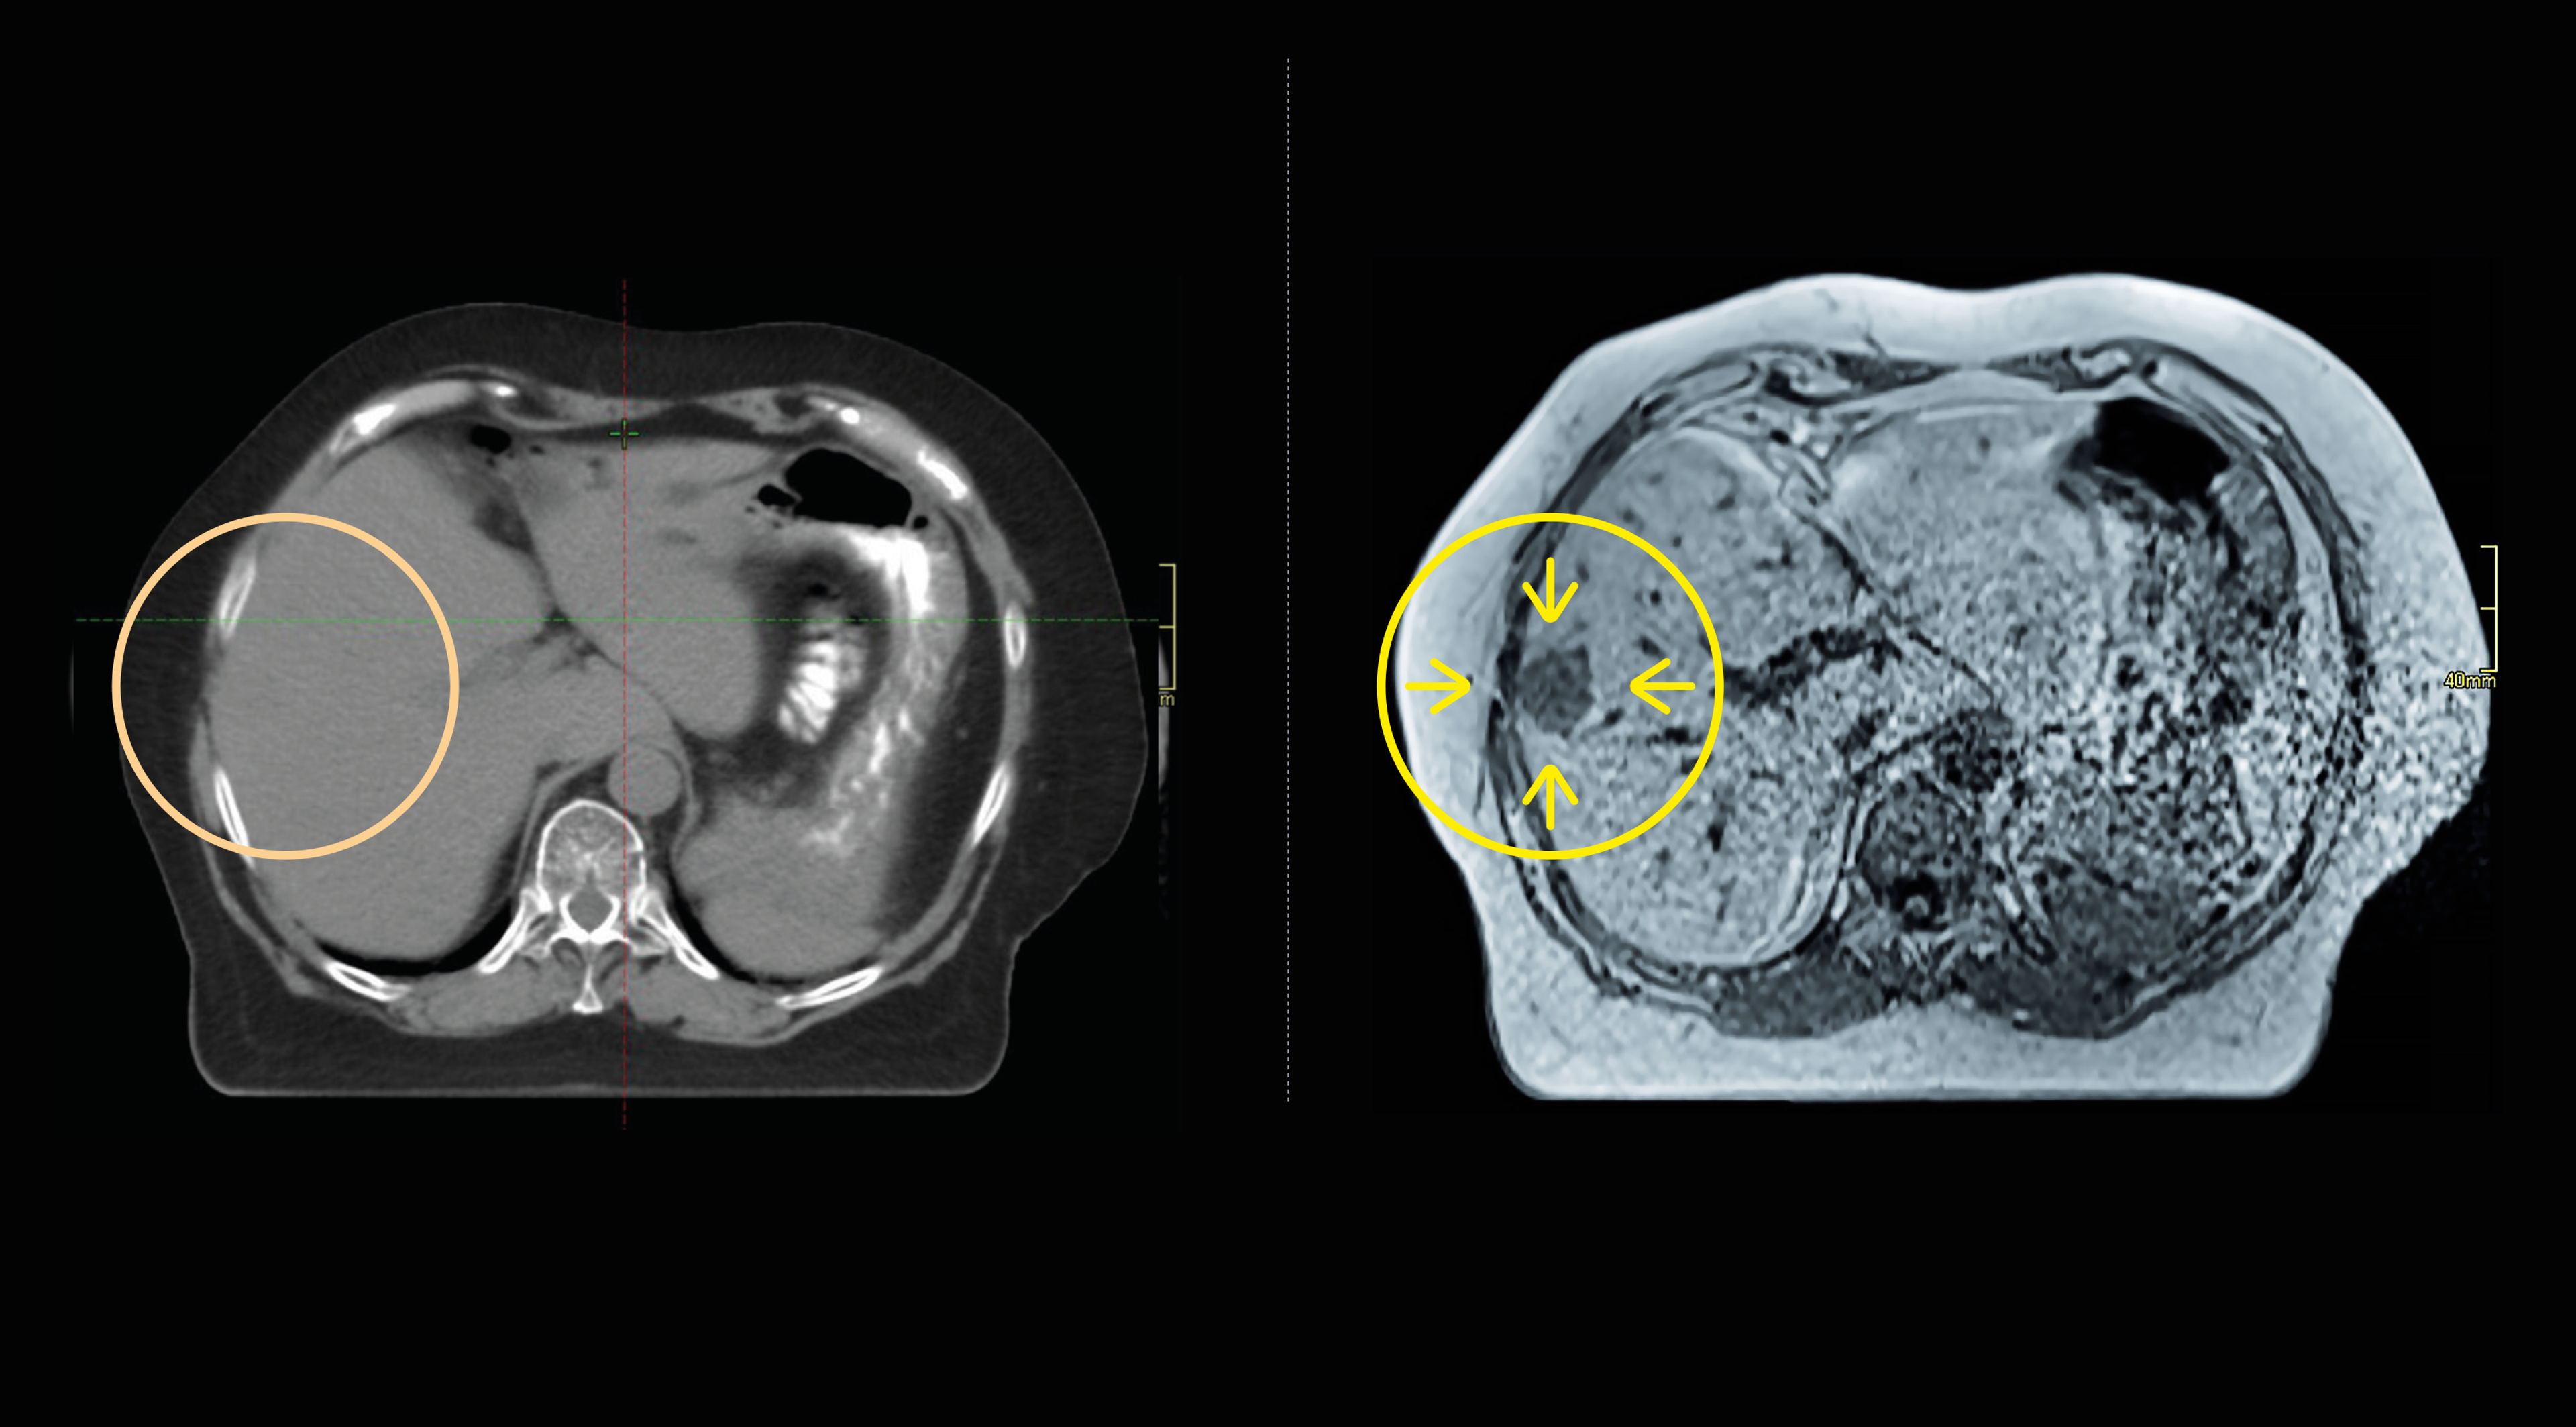

Standard CT scan of cancer patient

MRI scan of cancer patient

Benefits of MRI over CT

The MRI SIM allows for unprecedented precision in radiotherapy planning, particularly for complex cancers like those in the head, neck, and pelvis. This precision results in better targeting of tumours while sparing healthy tissue, leading to fewer complications and faster recovery for patients.

By enhancing the accuracy of radiotherapy, the MRI SIM improves treatment effectiveness, which is directly linked to higher survival rates, especially for difficult-to-treat cancers. Early and accurate treatment planning reduces delays, giving patients the best chance of beating cancer.

The MRI SIM minimizes damage to surrounding healthy tissues, significantly reducing short and long-term side effects of radiotherapy. This improves patients’ quality of life during and after treatment, reducing the burden of cancer care on individuals and their families.

The simulator will benefit 12–18 patients daily, with improved integration into clinical workflows and providing immediate benefits from day one. Its precision supports personalised treatment plans, enhancing outcomes for every patient treated.